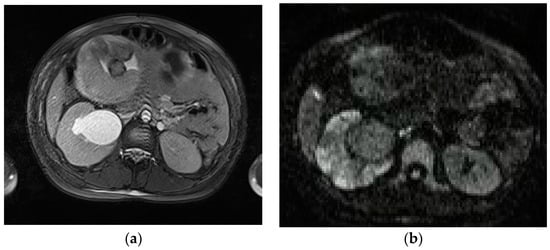

MRI demonstrates pancreatic enlargement and oedema, with reduced intensity on T1-weighted images and increased intensity on T2-weighted images (Figure 6).

Figure 6.

A 27-year-old pregnant woman with acute abdominal pain and elevated lipase levels (451 UI/mL). Coronal (a) and axial (b) T2-weighted sequences show peripancreatic fat stranding and fluid (arrows), interdigitating through pancreatic parenchyma. These findings are consistent with acute pancreatitis.

On DWI, acute early pancreatitis shows restricted diffusion and lower ADC values than the spared parenchyma [65]. In severe pancreatitis, necrotic foci within the parenchyma are hypointense on T1-weighted images and hyperintense on T2-weighted images, compared to the non-necrotic gland. Parenchymal haemorrhage can be detected at spotted or patchy high-signal intensity (like “salt”) on T1-weighted fat saturated sequences. Peripancreatic abnormalities, such as fluid collection, edema or fat stranding are better identified on fluid-sensitive sequences, appearing as high-intensity signals surrounding the gland. MRCP sequences acquired with respiratory gated-thin sections, are best suited to depict biliary and pancreatic ductal dilatation, allowing the detection of gallstones, shown as filling defects in the gallbladder and biliary tract [3,41,66]. The majority of pregnant patients with AP do not have complications. Gilbert et al. reported a complication rate of 1.44%, all of which were acute peripancreatic fluid collections (APFC) [67]. APFC occur in 50% of interstitial edematous pancreatitis. They are usually rounded with thin walls, often located in the lesser sac or anterior pararenal space. MRI is better than CT for detecting solid content or internal hemorrhage in APFC [68]. Vascular complications include arterial pseudoaneurism and venous thrombosis, most commonly involving splenic vessels; these abnormalities are typically assessed on contrast-enhanced MR angiography in non-pregnant populations, but can also be assessed with flow sensitive time-of-flight angiographic techniques [66].